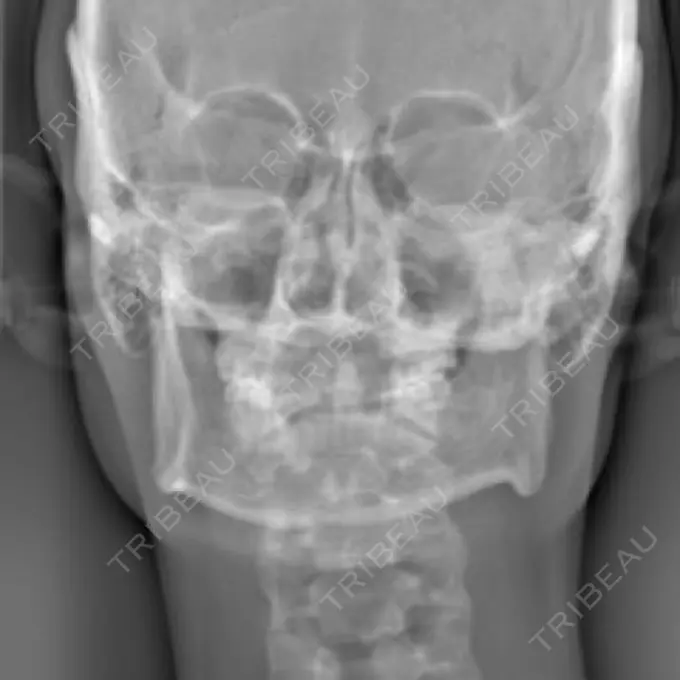

元々、左右差が酷かったので右側をオトガイ神経ギリギリまで切っていただき左はエラ部を中心に切りCTでも左右差が解消されていました。